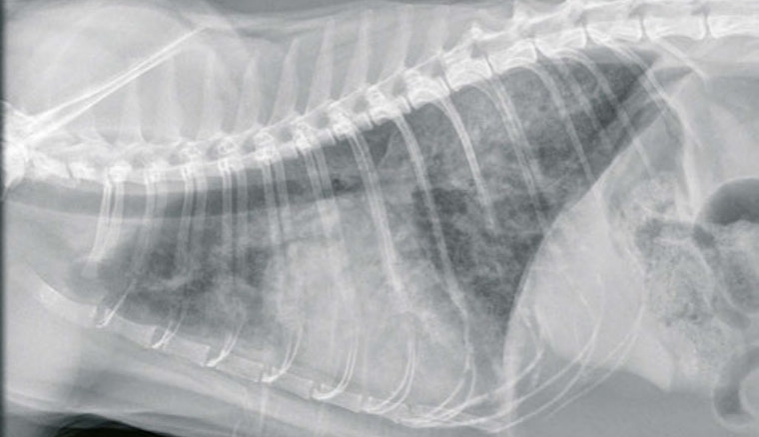

La valeur plasmatique du NT-proBNP est plus élevée lors de dyspnée d'origine cardiaque comparé aux dyspnées d'originerespiratoires ; ici un chat présentant un oedème aigu du poumon secondaire à une cardiomyopathie hypertrophique

© M. Faucher